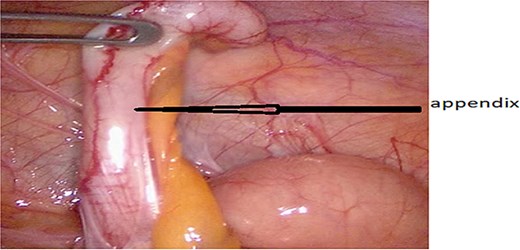

An urgent CT scan revealed situs inversus (Fig. 1) with left-sided high-positioned appendicitis (Fig. 2).

After obtaining informed consent and providing the patient with information about the case, he was transferred to the operating room after preparation, including rehydration, proton pump inhibitor (PPI), antibiotic therapy, and analgesia. Urgent exploratory laparoscopy confirmed the CT findings: retrocecal appendicitis with minimal peritoneal effusion (Fig. 3) in the Douglas pouch. A careful dissection of the appendix from its mesentery was performed, followed by appendectomy (Fig. 4), lavage, and drainage.